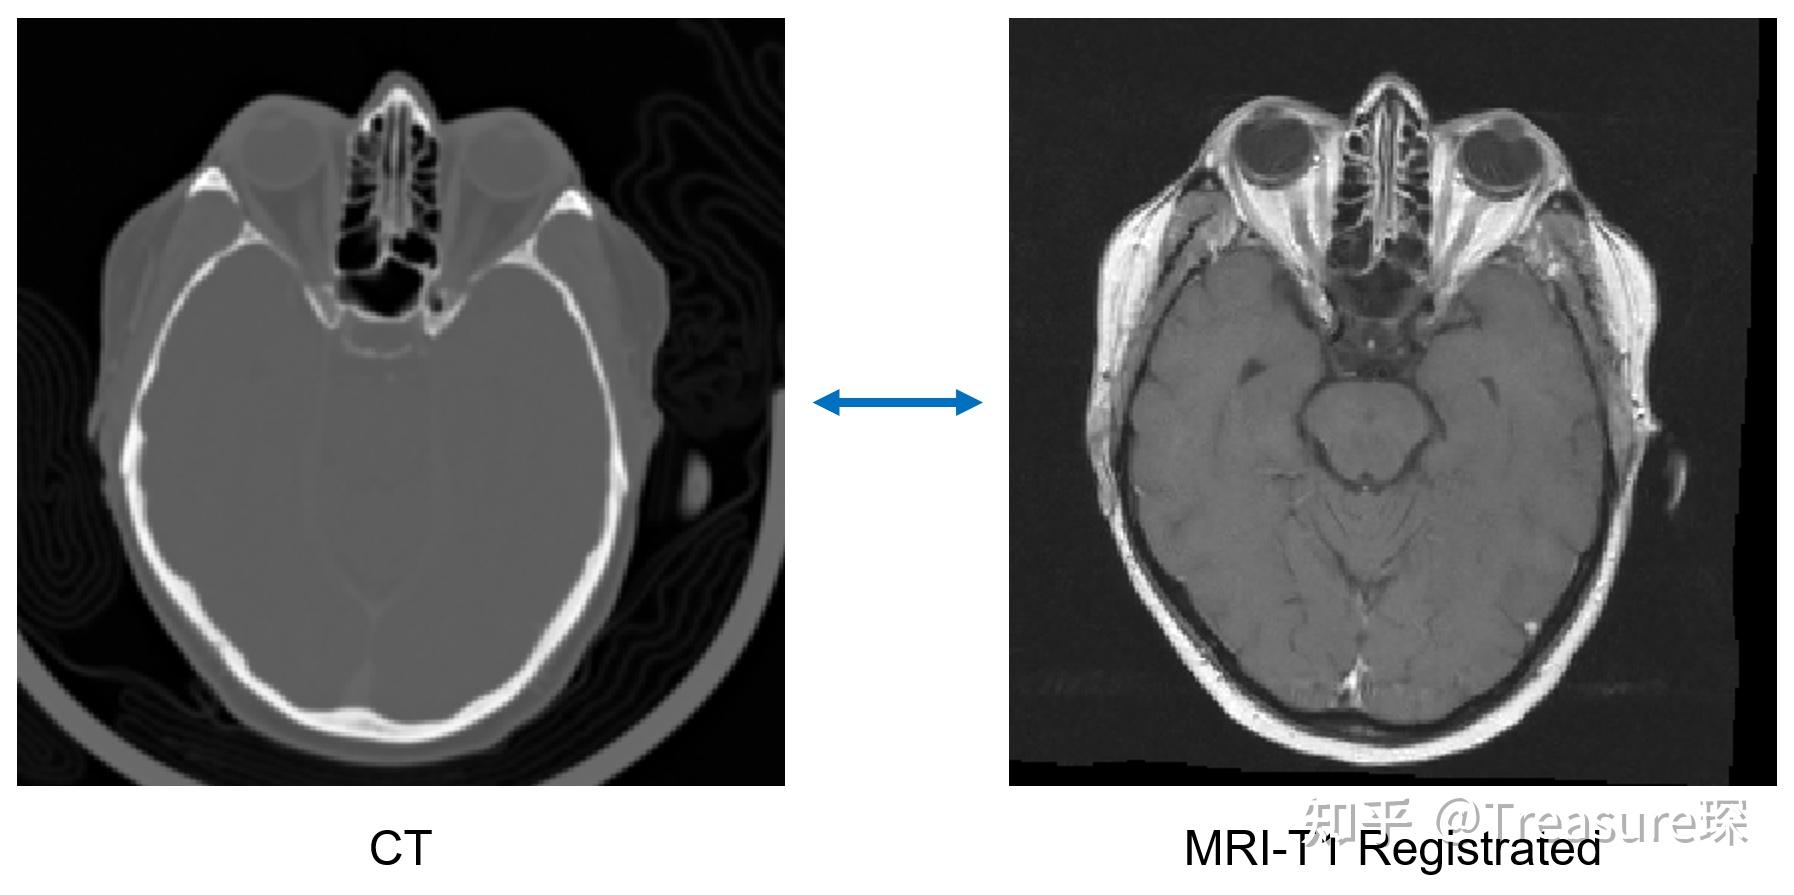

Python ANTs